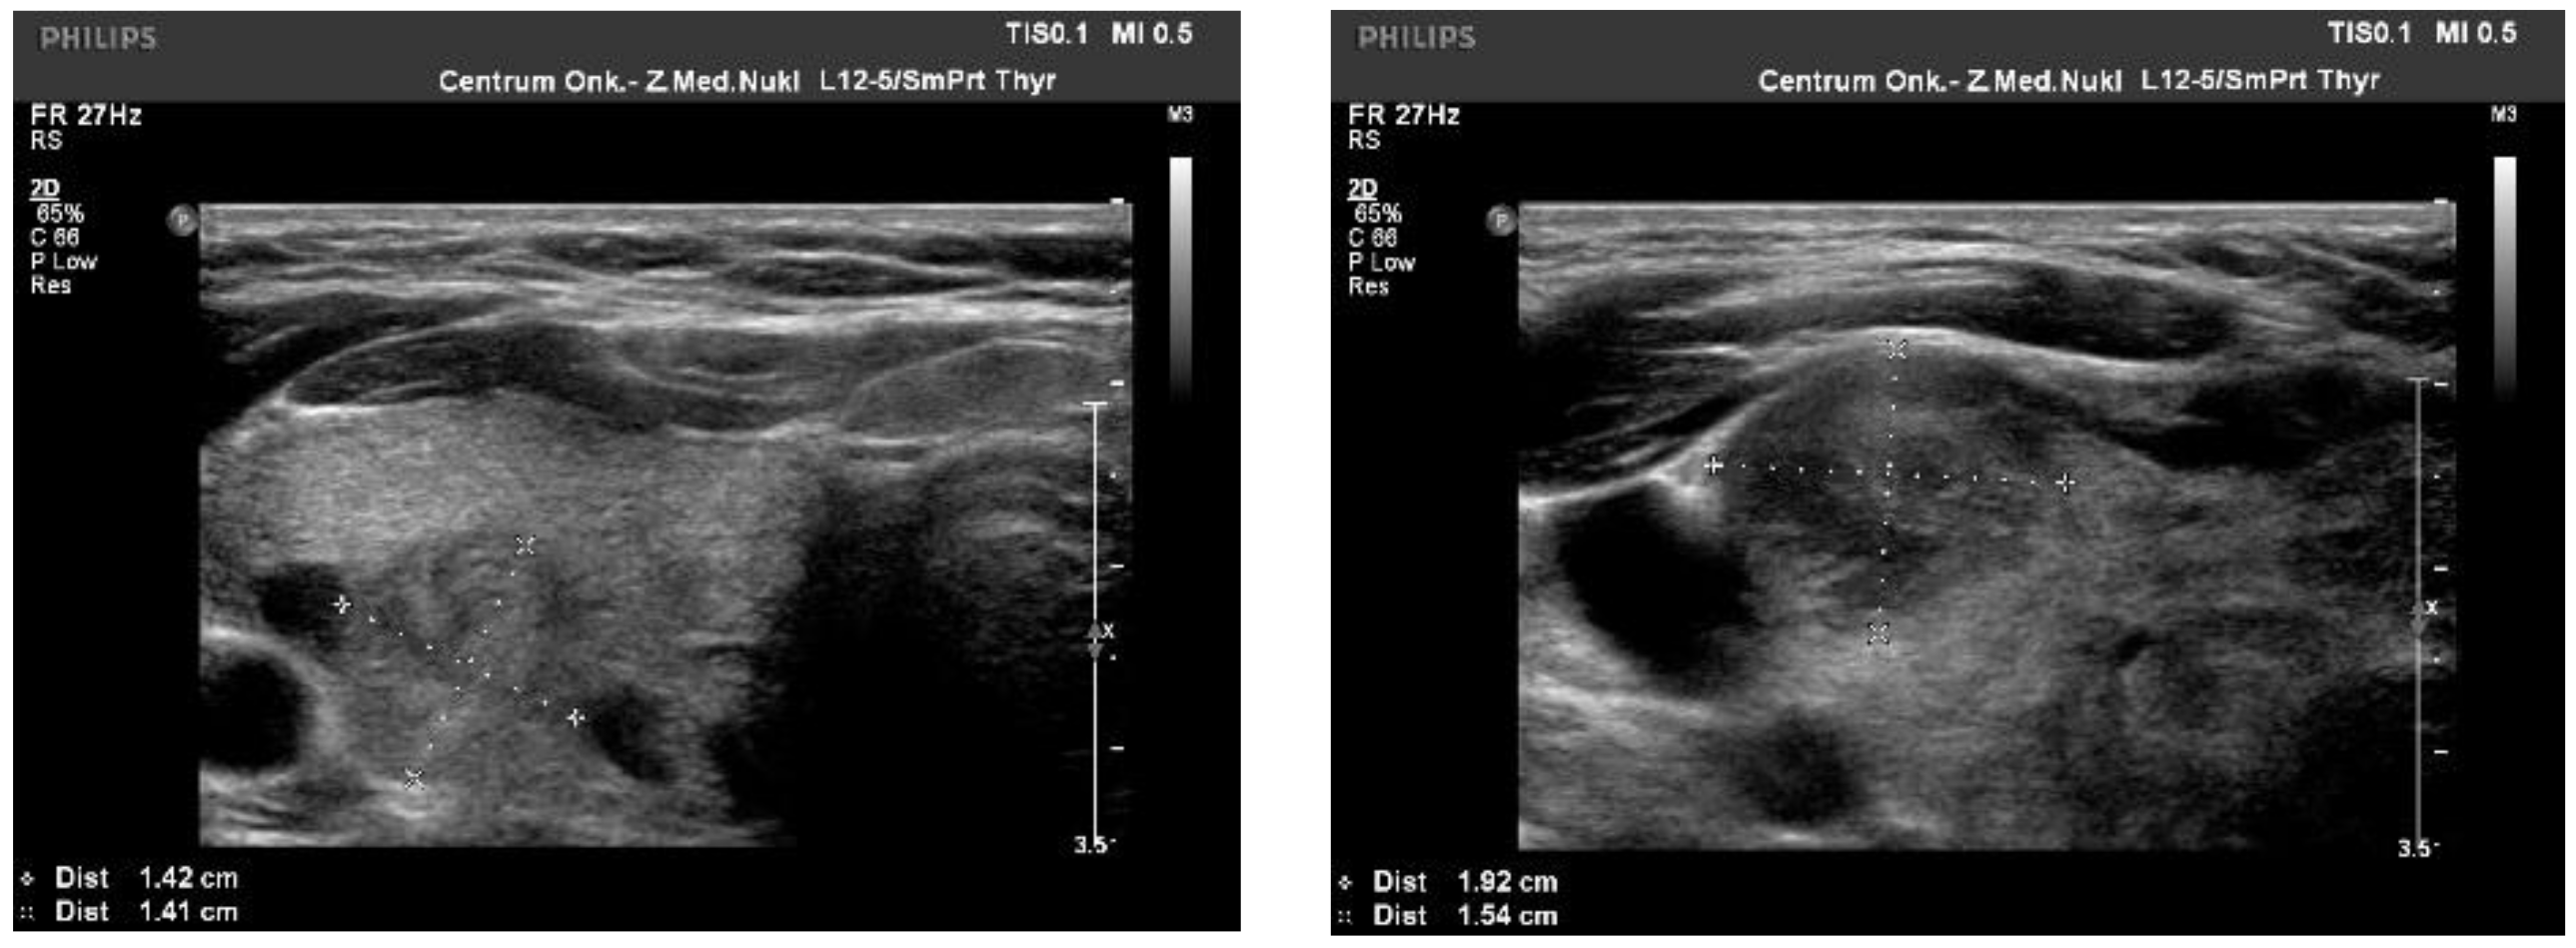

We observed the strongest correlation between hypoechogenicity (p-value < 0.05) and BRAF V600E positivity, although four more malignancy-associated features (taller-than-wide shape, blurred margins, microcalcifications, and absence of “halo”) were also more frequent in the BRAF V600E (+) group. PTC risk increased with a higher EU-TIRADS score (p-value = 0.04). US images of BRAF V600E (+) and BRAF V600E (−) PTCs are presented in Figure 2 and Figure 3, respectively.

Figure 3.

US image of BRAF V600E negative PTCs: solid structure (2 points), isoechogenic or slightly hypoechoic (1–2 point), taller-than-wide orientation (3 points), blurred margins (2 points), absence of calcifications (0 points)—8–9 points = TIRADS 5.